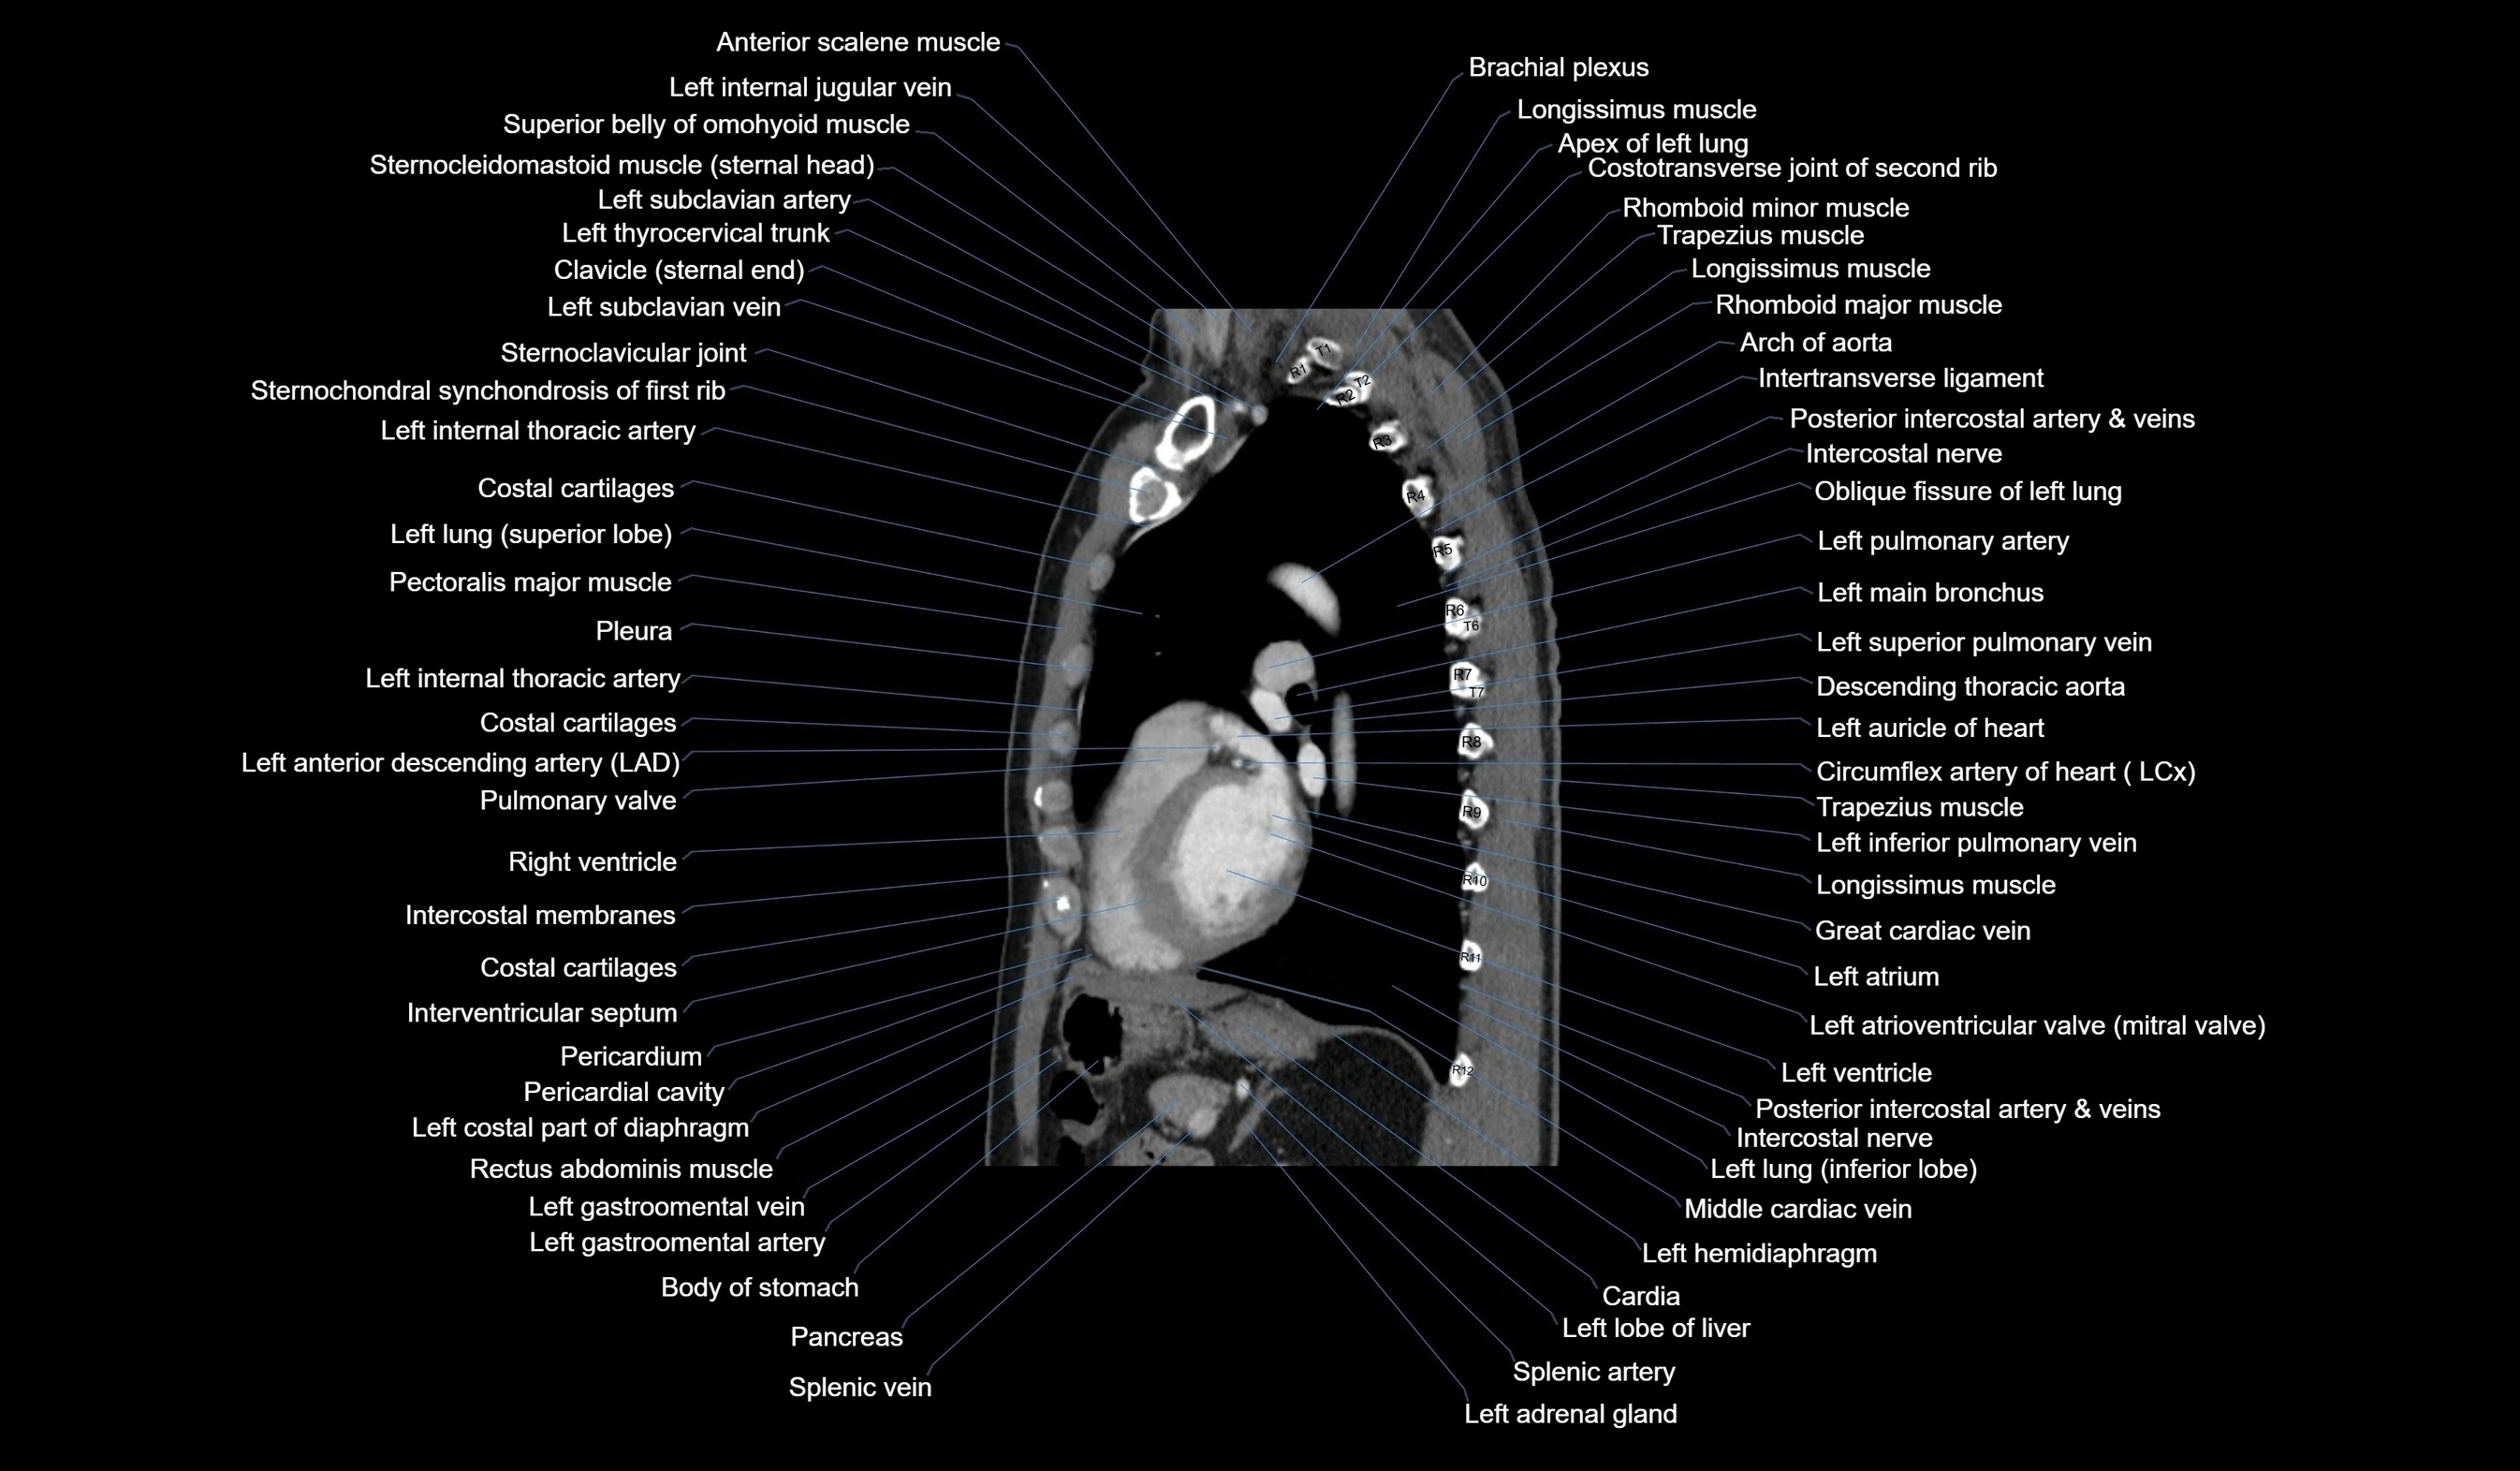

- T (Thoracic spine)